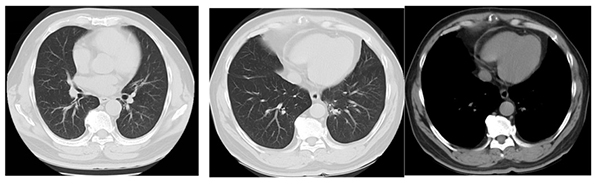

治疗7年(2025年6月)

2022年1月,复查胸部CT发现肺内新发转移灶,评估为疾病进展(PD),无进展生存期(PFS)为40个月。肺部新出现转移病灶位置难以进行肺穿刺活检,治疗团队迅速调整策略,在奥希替尼基础上联合化疗6周期(培美曲塞 + 卡铂),疗效评估为疾病部分缓解(PR),目前仍在奥希替尼持续治疗中,截至目前第2阶段持续稳定47个月,全程稳定87个月,已经超过7年3个月。